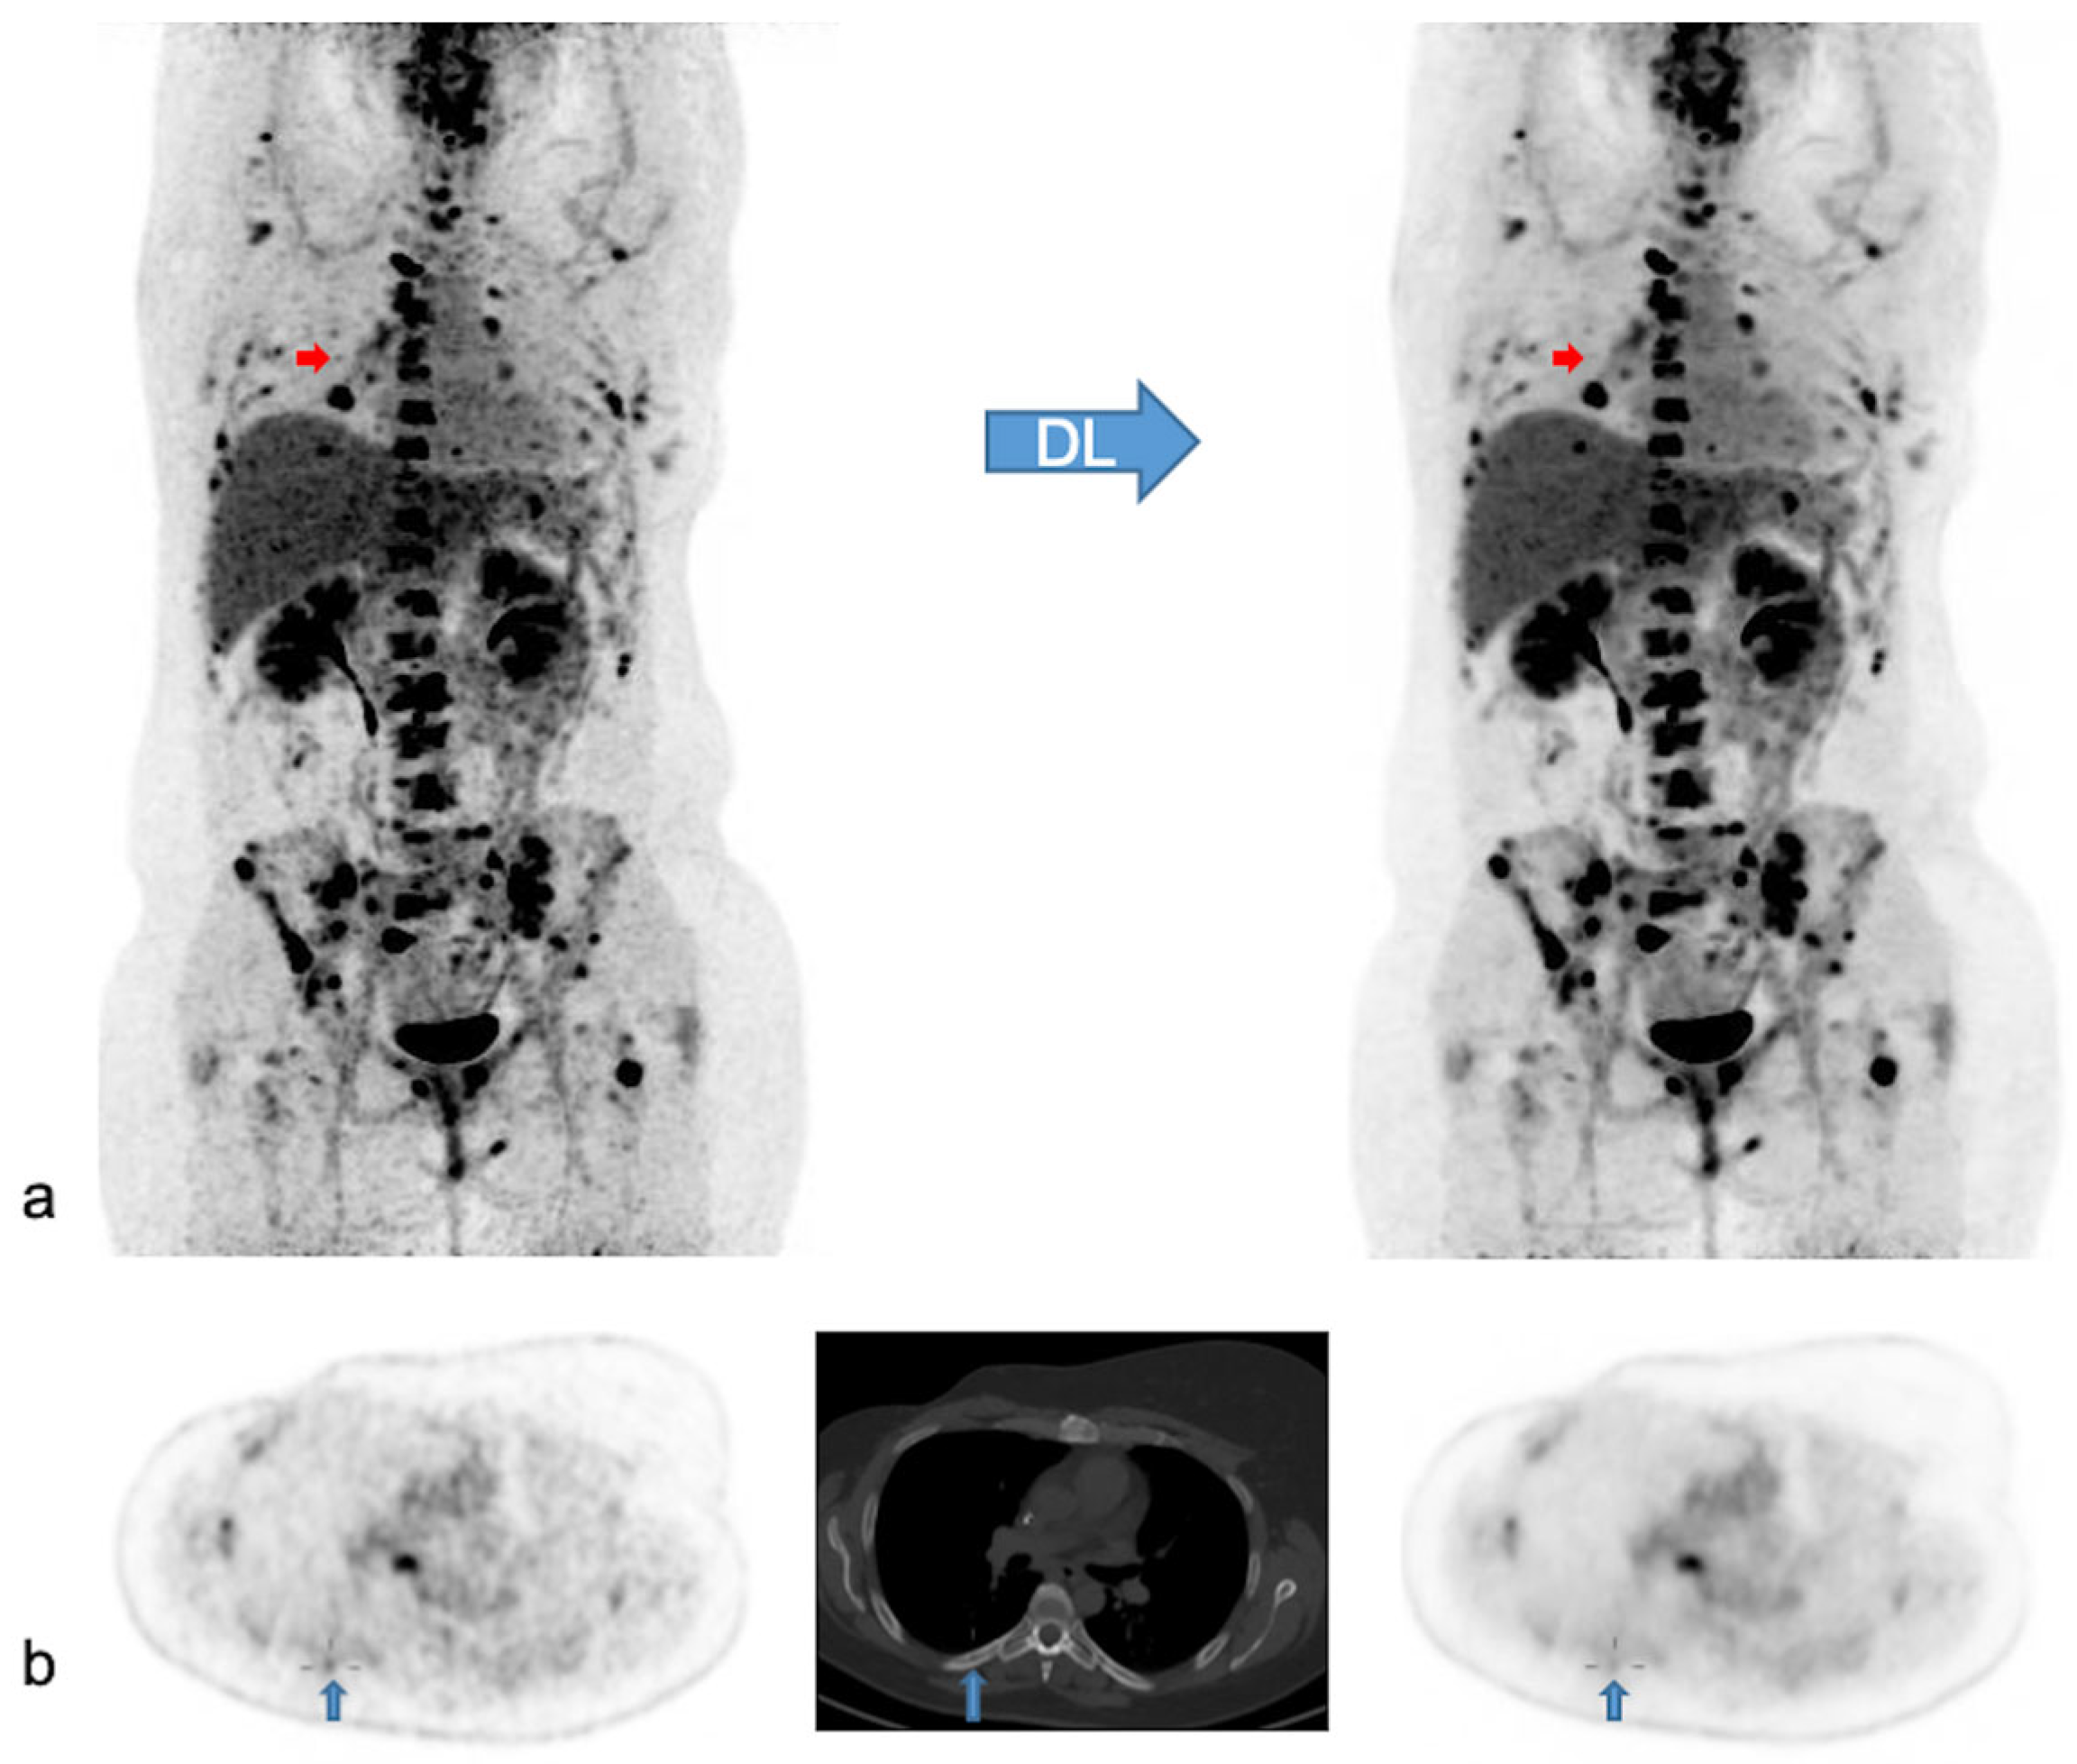

In 47 patients, PET findings were normal with both PET modalities. In the remaining 66 patients, a total of 371 lesions with increased [18F]FDG uptake were detected. Of these lesions, 369/371 lesions (99.5%) were visualized with both modalities, while two small, low-activity bone lesions were detected only with native PET. In addition, ease of detecting the remaining concordant lesions was judged not significantly different in most of the lesions (359/369; 97.3%), better with native PET in 8/369 (2.2%) or better with denoised PET in 2/369 (0.5%). In Figure 5 we illustrate the effect of PET denoising on lesion detectability.

Figure 5.

Native and denoised PET images of a patient with slightly better lesion detection with native PET. Legend: DL: deep learning processing by SubtlePETTM. A [18F]FDG PET/CT exam of a 37-year-old female patient, weight 105 kg, BMI 34 kg/m2 and FM 48 kg. She was referred for the follow-up of breast cancer with multiple (strongly) [18F]FDG avid bone and nodal metastases. In (a) MIP views are illustrated of native (on the left) and denoised PET (on the right). Almost all lesions were detected similarly in both PET modalities. Nonetheless, denoised images appeared less noisy, especially in the liver. Small red arrows in (a) depict a false negative small bone metastasis in denoised PET, further illustrated on axial PET/CT slices in (b) (upward blue arrows). This small low-activity focus corresponds to a lytic bone lesion measuring 4 mm on CT (b, upward blue arrows). This false negative lesion on denoised PET had no clinical impact.